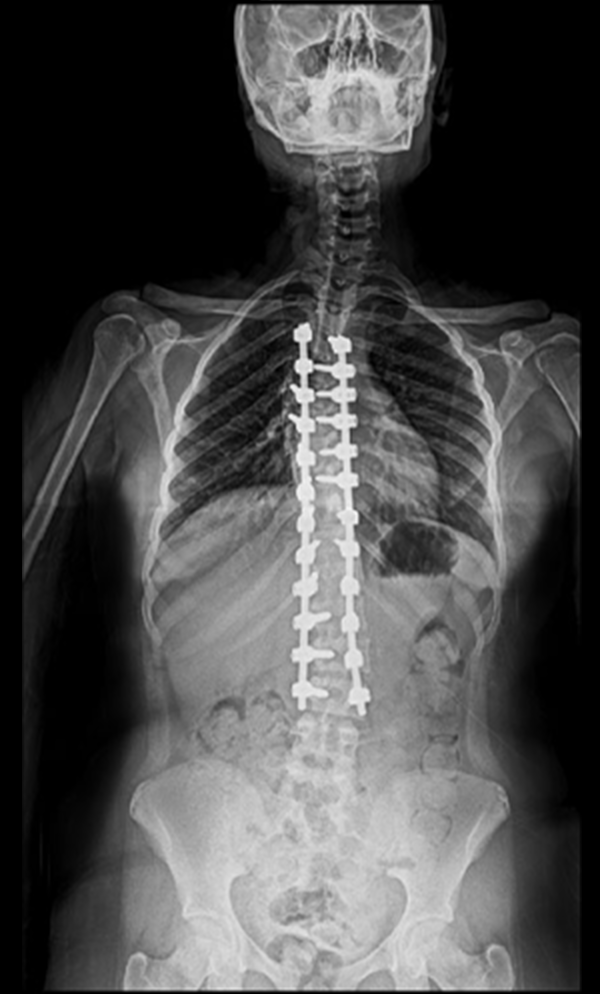

BEYOND RECOVERY : REAL STORIES

Gallery : Before - After